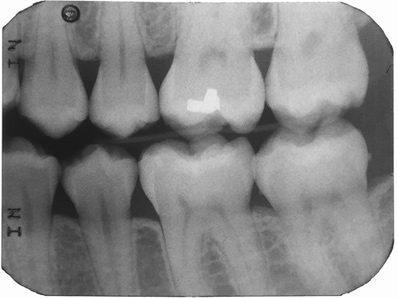

A 28-year-old woman, who previously had braces, had circumferential gumline decalcification (Figure 1) and wished to arrest lesions before they worsened (bitewing, Figure 2). The following protocol is consistent with the product instructions for the resin infiltration material from DMG America, which is the only commercially available resin infiltration system in the US.

Figure 13 shows a bitewing of a 7-year-old girl with Williams syndrome who had previously required treatment under general anesthesia (GA) in a hospital setting for treatment of caries in her primary teeth. An incipient lesion on the mesial of her lower right permanent first molar, tooth No. 30, was treated more conservatively, in office, with resin infiltration, which allowed her to avoid more invasive treatment and the possible need for another GA. The lesion was arrested (Figure 14) and has been stable for over 5 years.

Fig 2.  Circumferential gumline decalcification (Fig 1) and bitewing (Fig 2) of a 28-year-old woman.

Figure 2